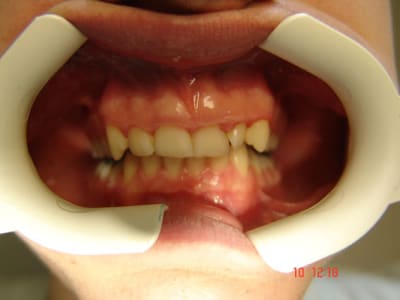

Pour la première photo, je lui ai demandé de ne pas fermer complètement de manière à mettre en évidence la déviation du point interincisif inférieur, à noter que les freins ne sont pas alignés non plus.

Au total: supraclusion incisive, déviation point interincisif inf vers la droite, décalage entre les bords libres des incisives / canines et le plan occlusal des molaires prémolaires, déglutition dents serrées. Pas de caries. Paro+/-. Hypotonie droite (cfr épaules).